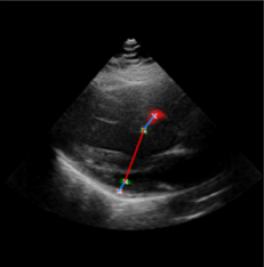

Left Ventricular Hypertrophy (LVH), one of the leading predictors of adverse cardiovascular outcomes, is the condition where heart’s mass abnormally increases secondary to anatomical changes in the Left Ventricle (LV) [10]. These anatomical changes include an increase in the septal and LV wall thickness, and the enlargement of the LV chamber. More specifically, Inter-Ventricular Septal (IVS), LV Posterior Wall (LVPW) and LV Internal Diameter (LVID) are assessed to investigate LVH and the risk of heart failure [21]. As shown in Figure 1 (a), four landmarks on a parasternal long axis (PLAX) echo frame can characterize IVS, LVPW and LVID, and allow cardiac function assessment. To automate this, machine learning-based (ML) landmark detection methods have gained traction.

It is difficult for such ML models to achieve high accuracy due to the sparsity of positive training signals (four or six) pertaining to the correct pixel locations. In an attempt to address this, previous works use 2D Gaussian distributions to smooth the ground truth landmarks of the LV [9, 13, 18]. However, as shown in Figure 1 (b), for LV landmark detection where landmarks are located at the wall boundaries (as illustrated by the dashed line), we argue that an isotropic Gaussian label smoothing approach confuses the model by being agnostic to the structural information of the echo frame and penalizing the model similarly whether the predictions are perpendicular or along the LV walls.